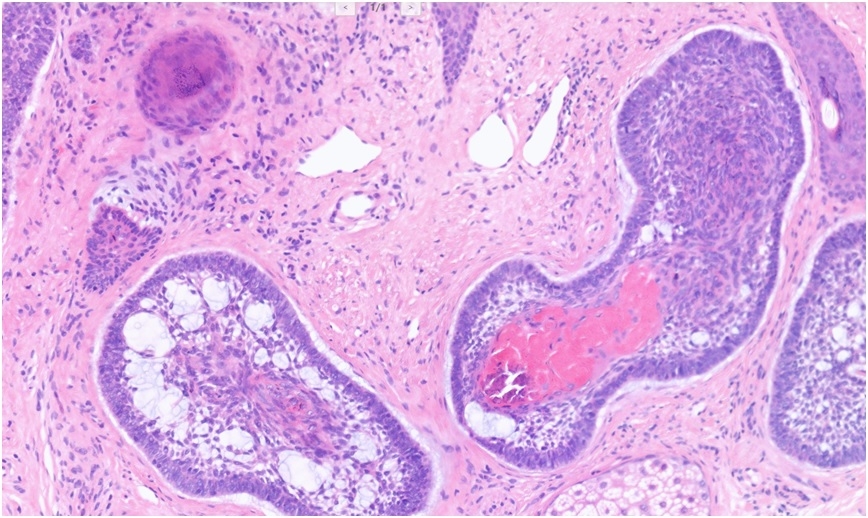

68M, 2VW - susp skin cancer. Lesion on tip of nose. Pigmented lesion with central regression, 4 mm in size. Hence removal of lesion using a 5 mm punch. DDx - naevus/melanoma. Sample 5 mm punch.